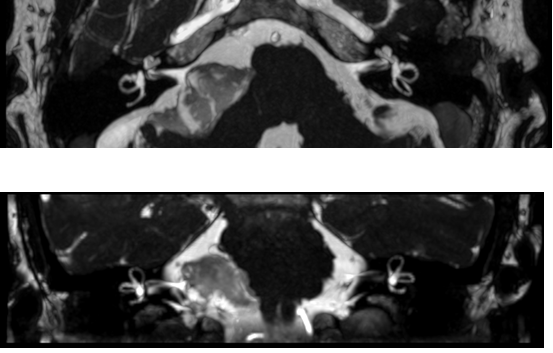

Tim 4G神经系统临床应用

Tim 4G高密度一体化头颈线圈提供高分辨率头部成像,更多的线圈单元数支持更高的iPAT并行采集因子,有利于减少EPI序列的磁敏感伪影。

CASE 3:表皮样囊肿